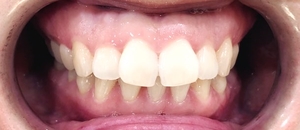

환자분의 원래 상태를 보겠습니다.

앞니가 많이 뻐드러져있어요.

다른 이에 비해서 위 앞니 두개만 많이 삐뚤었습니다.

단 2회 내원만에 과거 모습에서 이렇게 되신건데요

짜짠!!

요렇게 아래 사진처럼 고르게 되셨습니다.